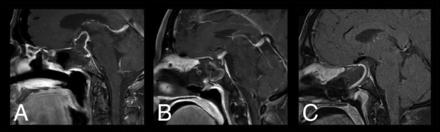

All patients underwent preoperative MR imaging within 48 hours of the operation, immediate postoperative MR imaging within 48 hours of the operation, and delayed postoperative MR imaging at least 3 months after the operation. Features evaluated included enhancement of the pedicle and flap (ie, no, weak, or bright enhancement) as evaluated on T1 postgadolinium sequences, flap thickness (in millimeters), flap adherence to the skull base (defined as absence or presence of gaps between the flap and skull base along the length of the flap), and diaphragma sellae descent for both immediate and delayed postoperative MRIs. Flap enhancement was quantified as follows: For each MR imaging, a 200 × 100 pixel window consisting of the flap and pedicle was extracted. Flap enhancement was calculated as the average pixel intensity (range, 0–255 pixels) of the extracted images. The 33rd and 66th percentile intensities were computed from the resulting list of enhancement values, which were used as thresholds to stratify flap and pedicle enhancement into 3 categories: no, weak, or bright enhancement. Representative figures demonstrating no, weak, and strong enhancement based on our objective criteria are shown in Fig 1.

Representative figures of no enhancement (A), weak enhancement (B), and bright enhancement (C).